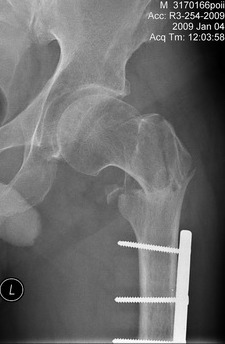

[Ortho] Перелом проксимального отдела бедра

АС> На снимке есть только дистальный отдел бедра, похоже, еще (или уже?) несросшийся на

АС> фоне DCS. Что за перелом проксимального бедра, пока информации нет.

Р-гр шейки

Имя     : Pochebyt 0901040001.jpg